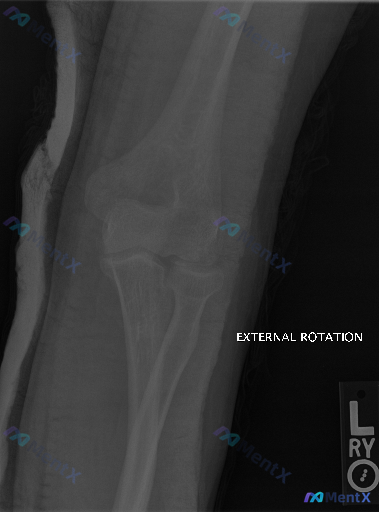

📷 影像情况:左肘关节外旋位X光片

- 投照位置标准,肱骨远端、桡尺骨近端骨皮质连续,未见明显骨折线、脱位或骨质破坏;

- 关节间隙清晰,无狭窄,无游离体;

- 关节周围软组织无明确肿胀,脂肪垫征(Sail sign)阴性;

- 也没有明显骨关节炎或异位骨化表现。

但给出的背景提示是「存在异常」—— 可能对应有临床症状(比如疼痛、活动受限),但平片确实没找到结构性问题。

📋答案:根据现有资料,左肘X光片本身无明确结构性异常;若临床有症状,最可能的异常来源依次为:1)X光不可见的软组织损伤(肌腱、韧带、滑膜);2)神经源性疼痛;3)极罕见且需进一步证据支持的隐匿性微细骨折/软骨损伤。